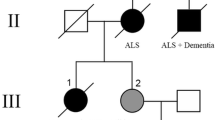

FTLD-TDP cases were divided into three groups: FTLD-TDP with C9ORF72 hexanucleotide repeat expansion (FTLD-C9ORF72; N = 17), FTLD-TDP with GRN mutation (FTLD-GRN; N = 13), and sporadic FTLD-TDP without a known mutation (sFTLD; N = 36). Of the 66 cases, 27 had a final clinical diagnosis of frontotemporal dementia (9 FTLD-C9ORF72, 5 FTLD-GRN, 13 sFTLD), 4 had progressive nonfluent aphasia (3 FTLD-GRN, 1 sFTLD), and 4 had frontotemporal dementia with motor neuron disease (1 FTLD-C9ORF72, 3 sFTLD). Twenty-three had a final diagnosis of clinically probable AD (7 FTLD-C9ORF72, 4 FTLD-GRN, 12 sFTLD). Other antemortem clinical diagnoses included progressive supranuclear palsy (N = 4; 2 FTLD-GRN, 2 sFTLD), corticobasal syndrome (N = 4; sFTLD), Pick’s dementia (N = 3; 2 FTLD-GRN, 1 sFTLD), Parkinson’s disease dementia (N = 3; sFTLD), dementia with Lewy bodies (N = 2; FTLD-C9ORF72), and normal pressure hydrocephalus (N = 1; sFTLD). Of the four FTLD-C9ORF72 cases with intermediate-to-high-likelihood Alzheimer-type pathology, three had a final clinical diagnosis of frontotemporal dementia and one had a diagnosis of clinically probable AD. All FTLD-C9ORF72 cases had widespread TDP-43 pathology, and six FTLD-C9ORF72 cases had additional degeneration of upper or lower motor neurons, or both. None of the FTLD-C9ORF72 cases had significant cerebrovascular disease, while three FTLD-GRN and six sFTLD cases had significant cerebrovascular vascular disease, defined as the presence of more than one micro-infarct, lacunar infarcts or subcortical arteriosclerotic leukoencephalopathy. Summary of FTLD-C9ORF72 patient demographics, pathologic features, and genetics can be found in Table 1.

The groups differed significantly (p < 0.001) in the frequency of recorded family history of degenerative disease defined as dementia, parkinsonism, or motor neuron disease. Given the brain bank referral basis of this series, some cases did not have information about family history and in only a subset of cases was family history collected in a systematic fashion. All of the FTLD-GRN cases had a positive family history (13/13) of neurodegenerative disease, while 3/17 FTLD-C9ORF72 cases, and 9/36 sFTLD cases had a positive family history. Accordingly, the pairwise comparisons were significant (p < 0.001) for FTLD-C9ORF72 versus FTLD-GRN, and for sFTLD versus FTLD-GRN, but not (p = 0.86) for FTLD-C9ORF72 versus sFTLD.